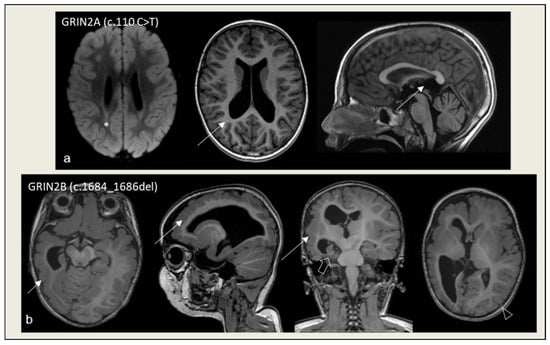

- Mangano, G.D.; Riva, A.; Fontana, A.; Salpietro, V.; Mangano, G.R.; Nobile, G.; Orsini, A.; Iacomino, M.; Battini, R.; Astrea, G.; et al. De Novo GRIN2A Variants Associated with Epilepsy and Autism and Literature Review. Epilepsy Behav. 2022, 129, 108604. [Google Scholar] [CrossRef] [PubMed]

- Thompson-Lake, D.G.Y.; Liegeois, F.J.; Braden, R.O.; Jackson, G.D.; Turner, S.J.; Morison, L.; Hildebrand, M.; Scheffer, I.E.; Morgan, A.T. Perisylvian and Hippocampal Anomalies in Individuals with Pathogenic GRIN2A Variants. Neurol. Genet. 2024, 10, e200129. [Google Scholar] [CrossRef] [PubMed]